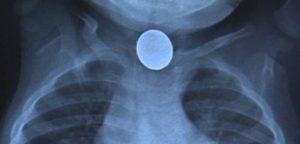

Хүүхдийн нас барсан шалтгааныг тогтоохоор цогцсыг задлан шинжилгээнд оруулахад, хүүгийн мөгөөрсөн хоолой цоорсны улмаас амь насаа алдсан болох нь тогтоогджээ. Талийгаач хүү хагас жилийн өмнө цагны зай залгисны улмаас өвдөж, улаан хоолойн мэс засалд ороод байсан ажээ.